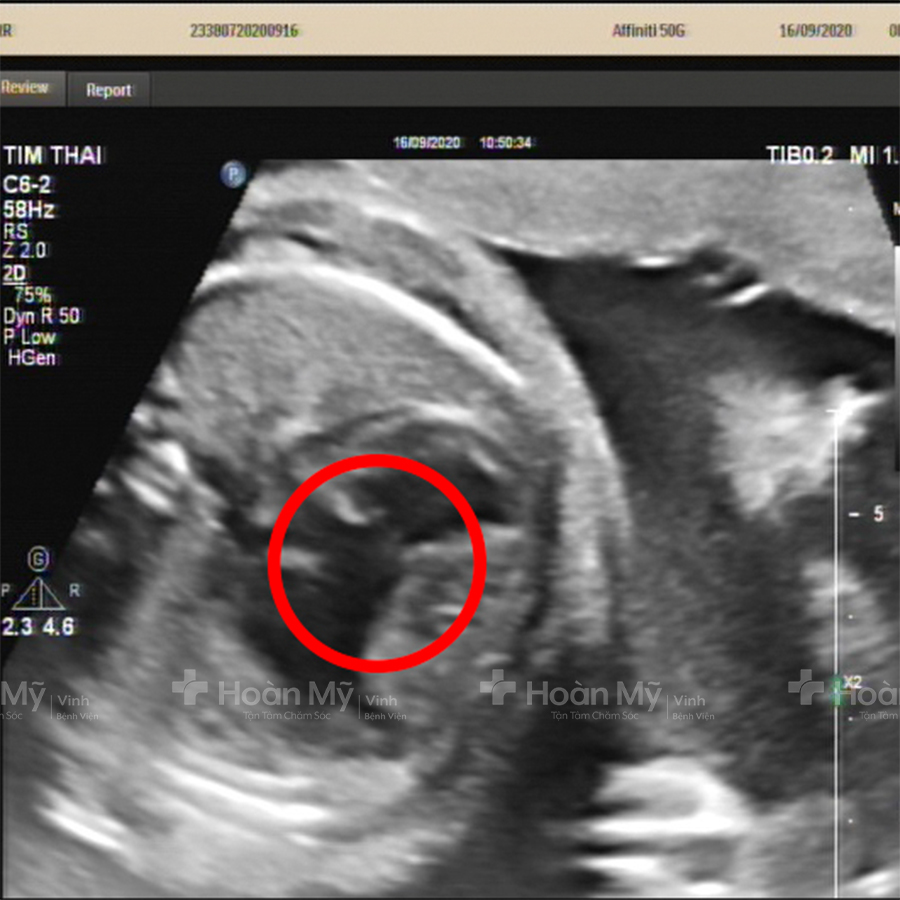

Siêu âm sẽ xác định được thai đã làm tổ trong tử cung hay chưa, và còn cho biết về tình thạng của thai nhi như bao nhiêu tuần tuổi, tim thai, kích thước,... Tuy nhiên, phôi thai 4 tuần chỉ bé bằng hạt gạo, nếu dùng phương pháp siêu âm thường rất khó thấy được.